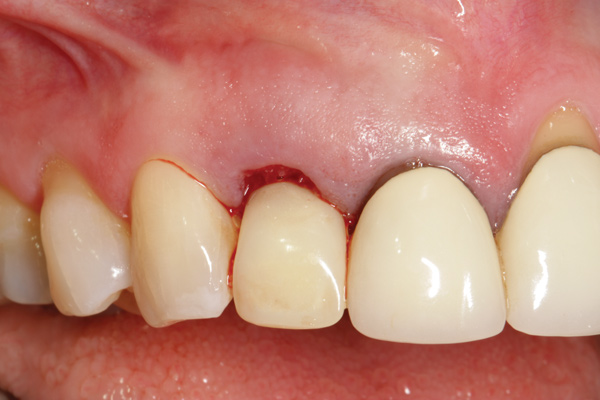

Fig 1. Clinical photograph showing significant issues related to implant midfacial mucosal recession and loss of interdental papillae. This is attributed to incorrect implant positioning (too buccal and too deep); several corrective surgeries resulted in interproximal bone loss, then loss of interdental papillae.

Figure 1

A minimum of 2 mm of facial bone thickness has been proposed as the “critical bone thickness” for the prevention of vertical height loss of the facial plate. It has been reported that when the distance of the buccal shoulder position of the implant to facial bone plate is below this critical thickness, an increased amount of facial bone resorption may be observed, which, in turn, may increase the chance of implant mucosal recession and failure (Figure 1). When the facial bone thickness is more than 2 mm from the implant buccal shoulder position, the likelihood of facial bone loss is decreased and the chance for alveolar bone stability is, therefore, increased.16

To predict peri-implant esthetic outcomes, Kois described five essential diagnostic keys that need to be assessed before removing a periodontally hopeless tooth (Figure 3 and Figure 4): (1) relative tooth position; (2) form of the periodontium; (3) periodontal biotype; (4) tooth shape; and (5) position of the osseous crest. Failing teeth that have a thick, flat gingival biotype, are square shaped, and have < 3 mm vertical distance from the position of the facial and interproximal crest have the lowest risk of developing recessions after implant placement.23 Therefore, implant surgery may be performed by either an open flap or flapless approach. However, teeth with a thin soft-tissue biotype, a highly scalloped gingival architecture, and a triangular shape that are positioned facially have less-predictable peri-implant esthetic outcomes. When a tooth presents with these unfavorable anatomical features, grafting procedures should be considered both before and after tooth extraction to prevent vertical loss and facial collapse of the gingival architecture.21 Flapless tooth extraction should be attempted in the esthetic zone to maintain blood supply from the periosteum and endosteum and maximize healing potential (Figure 5).44 In addition, several surgical protocols have been proposed to avoid peri-implant mucosal recessions, including 3-dimensional implant positioning,45,46 the use of platform-switching implants,47,48 and soft-tissue augmentation.8,49,50